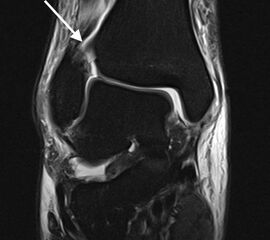

Magnetresonanztomographie (MRT)

Die Magnetresonanztomographie stellt aktuell den Goldstandard in der Diagnostik von Syndesmosenverletzungen dar (Szeimies 2013). Beschrieben sind eine Sensitivität von 100% und eine Spezifität von 93% bei Verletzungen des AITFL, sowie eine Sensitivität und Spezifität von 100% bei Verletzungen des PITFL. Darüber hinaus ermöglicht das MRT weitere ligamentäre, chondrale oder intraossäre Verletzungen zu detektieren. Bei chronischen Syndesmosenverletzungen sollte eine MRT-Diagnostik mit Kontrastmittel (KM) intravenös durchgeführt werden, da diese eine höhere Spezifität und Sensitivität im Vergleich zur nativen MRT-Bildgebung aufweist. Durch die zusätzliche Gabe von KM können durch eine Mehranreicherung des KM im Bereich der Syndesmose Rückschlüsse auf das Vorhandensein einer chronische Instabilität gezogen werden 41.